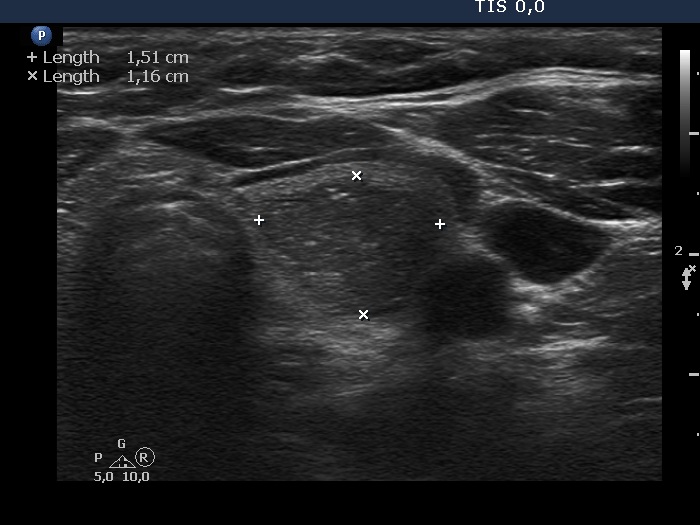

Ultrasonography. The thyroid was echonormal. There was a hypoechoic lesion in the left lobe. It was equivocal whether the lesion was composed of multiple nodules, therefore most of the lobulations seen on the surface of the mass were of questionable origin. However, there were protrusions in the ventral and medial part of the mass which were suspicious being pathological lobulations.